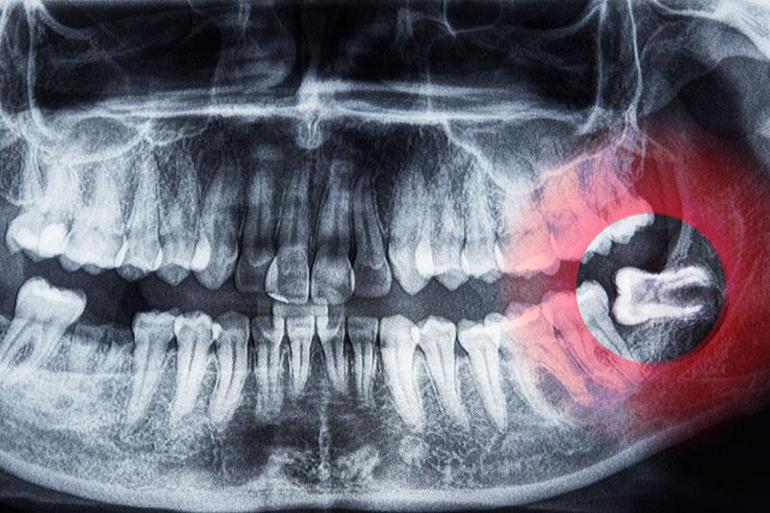

Betül Yasemin Keskin / Milliyet.com.tr – Yirmilik yaş dişleri olarak bilinen üçüncü azı dişleri bir vakitler çiğneme sürecine büyük bir katkı sunsa da vakitle bu fonksiyonunu kaybetmiş dişlerdir. Hem alt hem de üst çenede bulunan toplam dört adet 20’lik diş birden fazla kişi için epeyce can sıkıcıdır. Genelde 17-25 yaşları ortasında bir anda beliriveren ve çıkmaya çalışırken ağrı veren yirmilik diş birçok vakit cerrahi bir operasyon sonucu alınır. Kimileri 20’lik diş çıkarma konusunda şanslı olurken kimilerinin endişeli düşüdür. Lakin yapılan son bilimsel araştırmalar yirmilik dişin mucizevi gücünü ortaya çıkardı. Yapılan araştırmalara nazaran yirmilik dişin pulpa kısmı (sinir liflerini ve kan damarlarını destekleyen bağ dokusu) nörolojik hastalıklardan kardiyovasküler hastalıklara, ortopedik hastalıklardan göz hastalıklarına kadar birçok sıhhat problemine çözümcül bir yaklaşım sunabilir.

20’lik dişlerden alınan kök hücrenin birçok hastalığın tedavisinde kullanılabileceğinin altını çizen Doç. Dr. Münir Demirel, Parkinson, Alzheimer, spinal kord (omurilik) yaralanmaları üzere nörolojik hastalıklarda, kalp krizi sonrası kalp dokusunun tamiri üzere kardiyovasküler hastalıklarda, kemik kırıkları, kıkırdak rejenerasyonu üzere ortopedik uygulamalarda, diş hekimliği ve çene cerrahisinde, diyabet, karaciğer ve böbrek hastalıkları üzere sistemik rahatsızlıklarda kullanabileceğini iletti. En çok dikkat çeken tedavi metotlarından bir tanesi de 20’lik dişin göz naklinde de tedavi edici olması. Kornea naklinin işe yaramadığı durumlarda, hastaların dişlerinden yapılan özel bir protez görme yetisinin yine kazanılmasına yardımcı oluyor. Osteo-odonto-keratoprotez (OOKP, ismi verilen görme yetisini kaybetmiş lakin kornea nakli yapılamayan hastalarda uygulanan ileri seviye bir tedavi metodu olan bu süreci Doç. Dr. Münir Demirel şu şekilde anlattı: